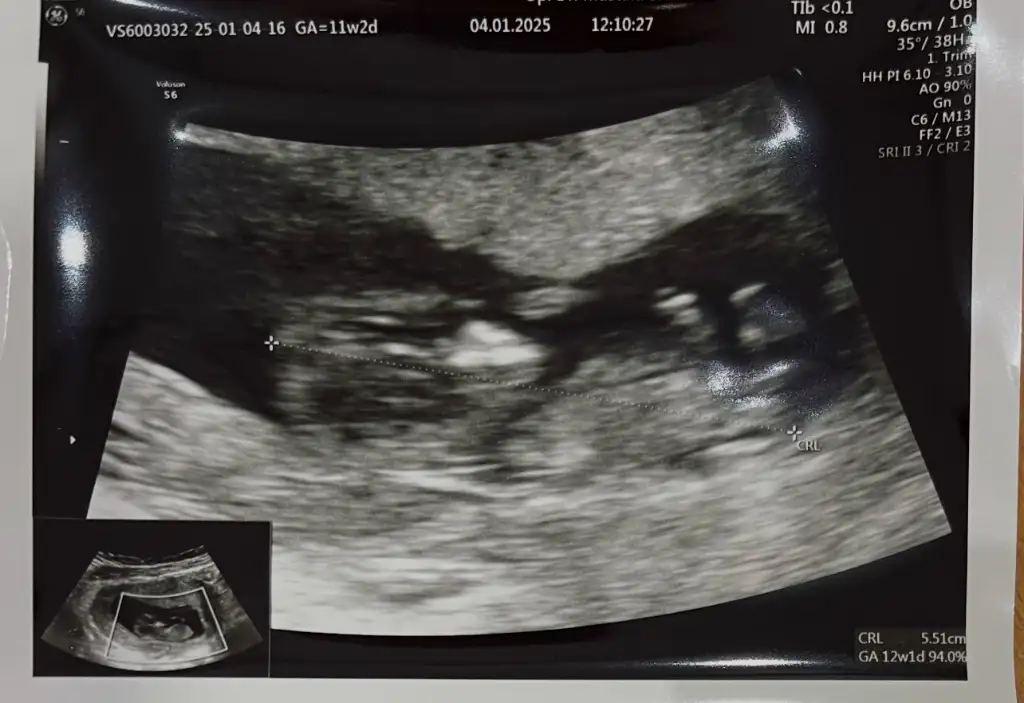

Merhaba 11+2 haftalık cinsiyet tahmini alabilir miyim rica etsem?

Merhaba canım hayırlı uğurlu olsun Rabbim sağlıklı sıhhatli kucağına almayı nasip etsin 🥰 kese şeklinden dolayı erkeğe benzettim , erkek kesesi 🫘 gibi olur kızın kesesi de yuvarlak gibi tabi bu bi tahmin yanlışta çıkabilir söyleyeyim şimdiden 🥰😂🤗

Yanılmıyorsam bu bebiş oğluşa benziyor Rabbim gönlünüze göre versin hayırlı olsun bu arada Analı babalı büyüsün inşallah 🤲🏼💞